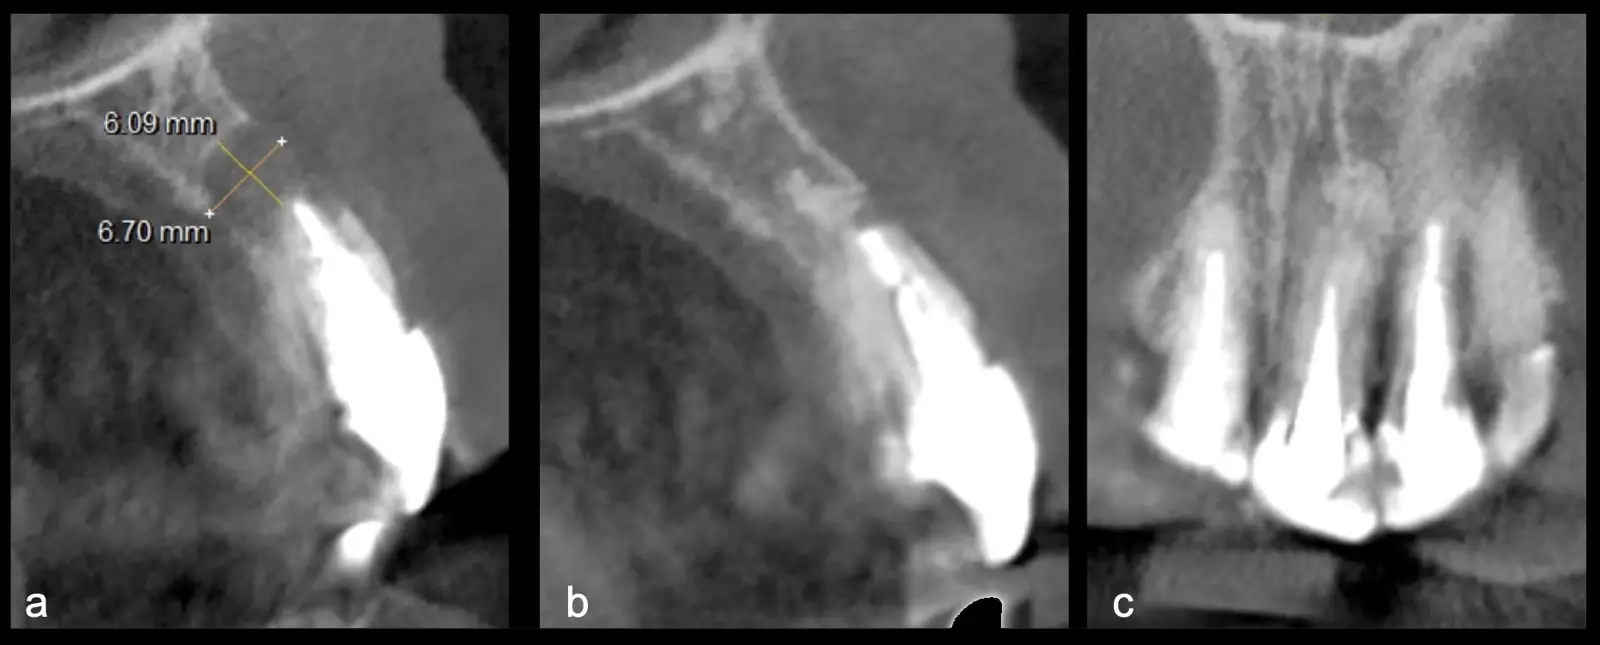

El origen puede ser bacteriano (colonias bacterianas persistentes4, patología periodontal asociada5, reinfecciones por falta de sellado coronal), mecánico (preparación deficiente, fractura de instrumentos, fracturas radiculares6, extravasación de material de obturación7 con ó sin compromiso de estructuras vecinas) y anatómico (conductos accesorios poco permeables o calcificados)8 (Figuras 1 - 4).

La microcirugía endodóntica apical busca conservar la mayor cantidad de longitud de raíz y de hueso circundante sano para no afectar la estabilidad de la pieza.11 Por ello, es ideal el uso de microscopios, elementos de magnificación, instrumental específico (insertos de ultrasonido endodónticos) y materiales de sellado eficientes para el tratamiento retrogrado. Su éxito es alto y evidencia una cicatrización ósea completa en el 74% de los casos al año de tratamiento.12 Cabe destacar que este logro está asociado también, a predictores propios de cada paciente, como la edad, tipo de pieza, profundidad de sondaje y extensión de la lesión.1 El uso complementario de la tomografía computarizada es resaltante como el instrumento imagenológico de elección para la etapa de planificación microquirúrgica,13 ya sea para una ejecución a mano alzada o con guías prefabricadas.14,15

Una vez limpia la zona apical, se corrobora la integridad de la raíz y se evalúa el grado de extensión de la lesión. Si el defecto óseo es pequeño, se procede a realizar la preparación del conducto y obturación retrógrada de ser el caso. Si el defecto óseo es de gran tamaño e inaccesible a los insertos, se procede a realizar un corte de por lo menos 3 mm de ápice radicular conteniendo los posibles conductos aún infectados11 empleando habitualmente insertos de borde aserrado con/sin marcas de medición para un trabajo seguro7 (Figura 7).